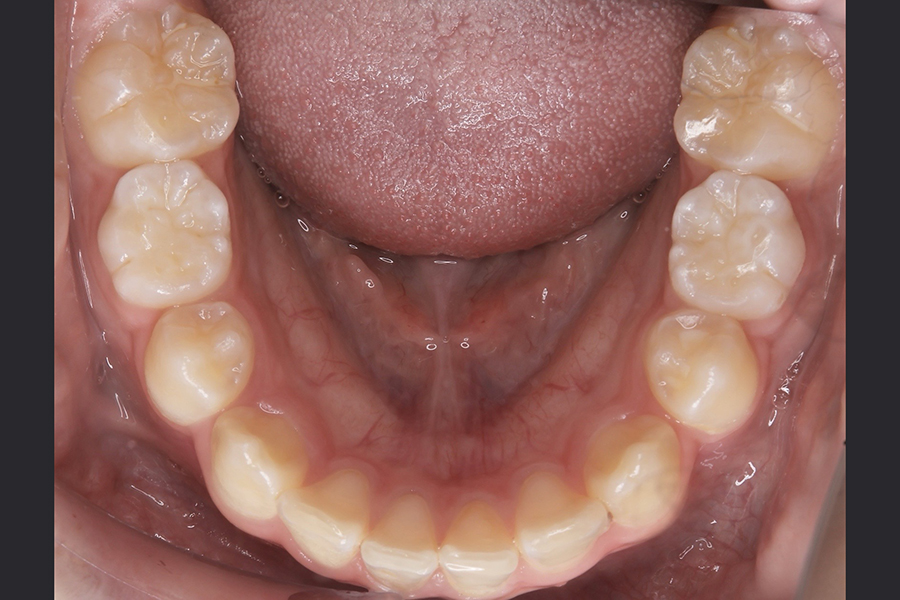

FDT症例② S.Hくん(10)

治療前

相談内容 |

うつ伏せ寝、口呼吸が気になる 歯並びの悪さ |

カウンセリング・診断結果 |

口呼吸、低位舌、上下顎劣成 |

行った治療内容 |

FDT(筋機能矯正治療/マイオブレース治療) |

治癒期間 |

2024.8.31〜 |

費用 |

385,000円(税込) |

治療リスクについて |

・お子様・保護者の協力が必要。 |

担当者からのコメント |

頑張り屋さんで真面目なHくん。正面から見ると一見綺麗ですが、横から見た時の前歯の出っ張りや永久歯の生えるスペースがないためFDTを始めました。 |